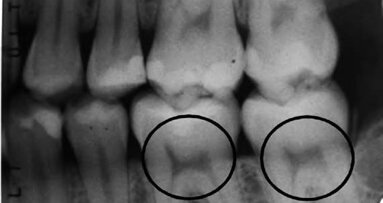

Τα ανθρώπινα δόντια εμπεριέχουν στοιχεία για την έλλειψη της βιταμίνης D και Καναδοί ...